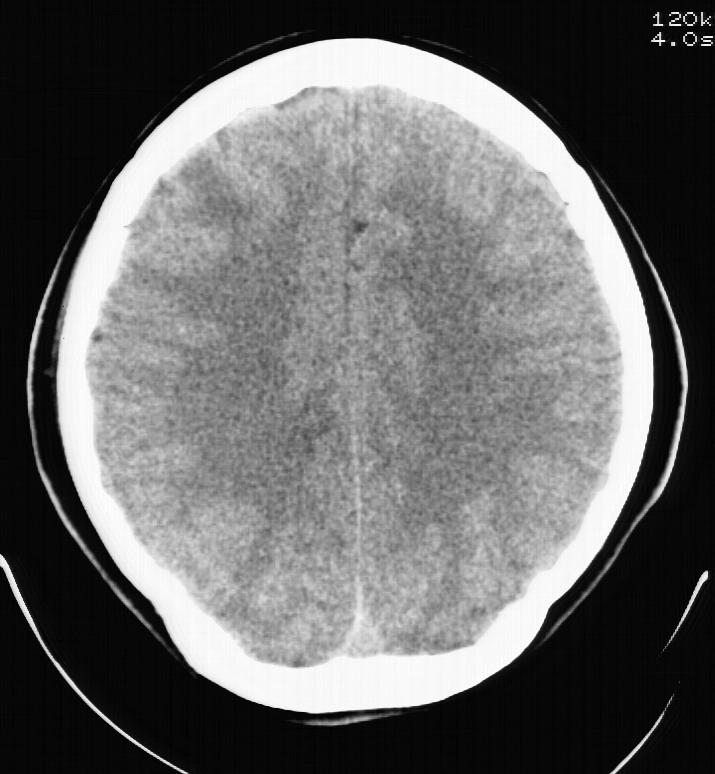

标题: CT5853:右额叶上部占位请会诊

女,34岁,自述头晕胀2年,近期感精神恍惚,无发热,实验室检查阴性。

右额叶上部皮质区见类圆形低密度区,边界不清,无强化,无钙化。

支持大多数战友的意见,1级星形细胞瘤。